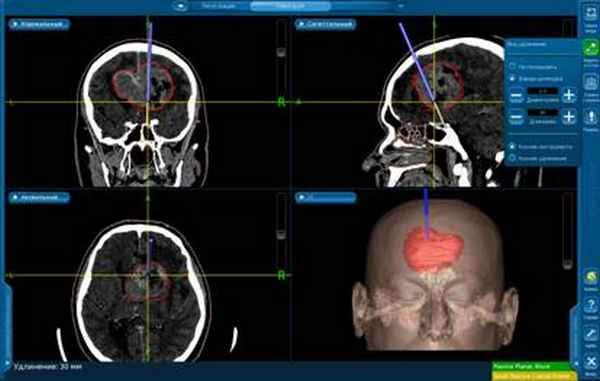

Выполнено предоперационное планирование с учетом данных КТ-ангиографии.

КТ ангиография головного мозга (22.10.15): в левой лобно-теменной области парасагиттально, прилегая к мозговым оболочкам, определяется интенсивно накапливающее контраст и обильно кровоснабжаемая опухоль, размером 53х40,7х37мм. Смещение срединных структур 5,8 мм.

Учитывая высокую васкуляризацию опухоли и риск массивной интраоперационной кровопотери, принято решение о проведении эмболизации сосудов опухоли микроэмболами.

29.10.2015 была выполнена операция: микрохирургическое удаление опухоли под контролем нейронавигации и применения нейрофизиологического мониторинга.